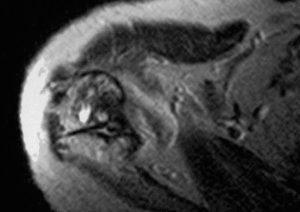

Las causas extrínsecas del atrapamiento del espacio subacromial se deben a anomalías en la bóveda acromial y a la articulación acromioclavicular. Bigliani y Morrison4 describieron en cadáveres tres tipos de acromion: el tipo I o plano, el tipo II o curvo y el III o en forma de gancho. Sólo el 39% de las articulaciones analizadas presentaron un acromion tipo III, si bien el 70% de éstos presentaban una lesión del manguito rotador (fig. 2). Por su parte, Gerber et al10 relacionaron el síndrome subacromial crónico con el atrapamiento subcoracoideo en relación con el papel de la apófisis coracoides y en sus tres formas, idiopática, yatrogénica y traumática.

Figura 2. Correlación radiográfica y de resonancia magnética (RM) de un acromion tipo III.